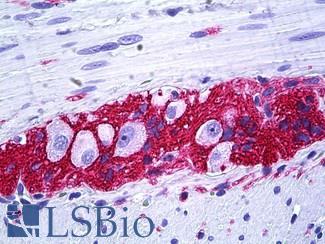

EGFR

Anti-EGFR antibody IHC of human skin. Immunohistochemistry of formalin-fixed, paraffin-embedded tissue after heat-induced antigen retrieval. Antibody LS-B2914 concentration 5 ug/ml.